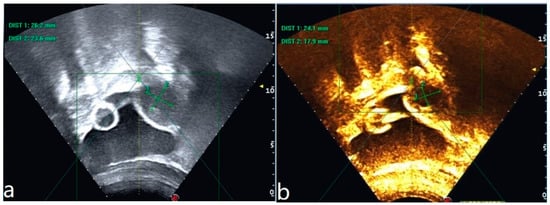

Figure 2.

Ultrasound image of the lesion before HIFU treatment (a). Ultrasonography after HIFU treatment shows no perfusion of the lesion (b).